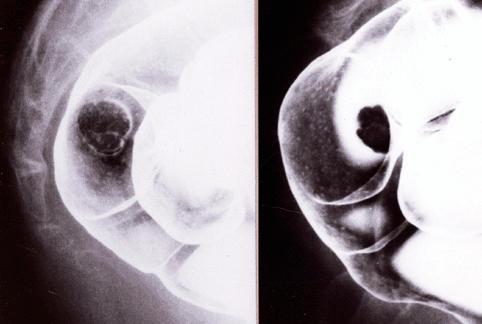

Type 0-1s (sessile type) early colorectal cancer without stalk formation revealed by movement of barium around the polypoid lesion.

Malignant epithelial tumor/Adenocarcinoma

Large intestine(Colon)/Rectum

X-ray

Type 0/I (Is) Sessile type

15 - 19

submucosa